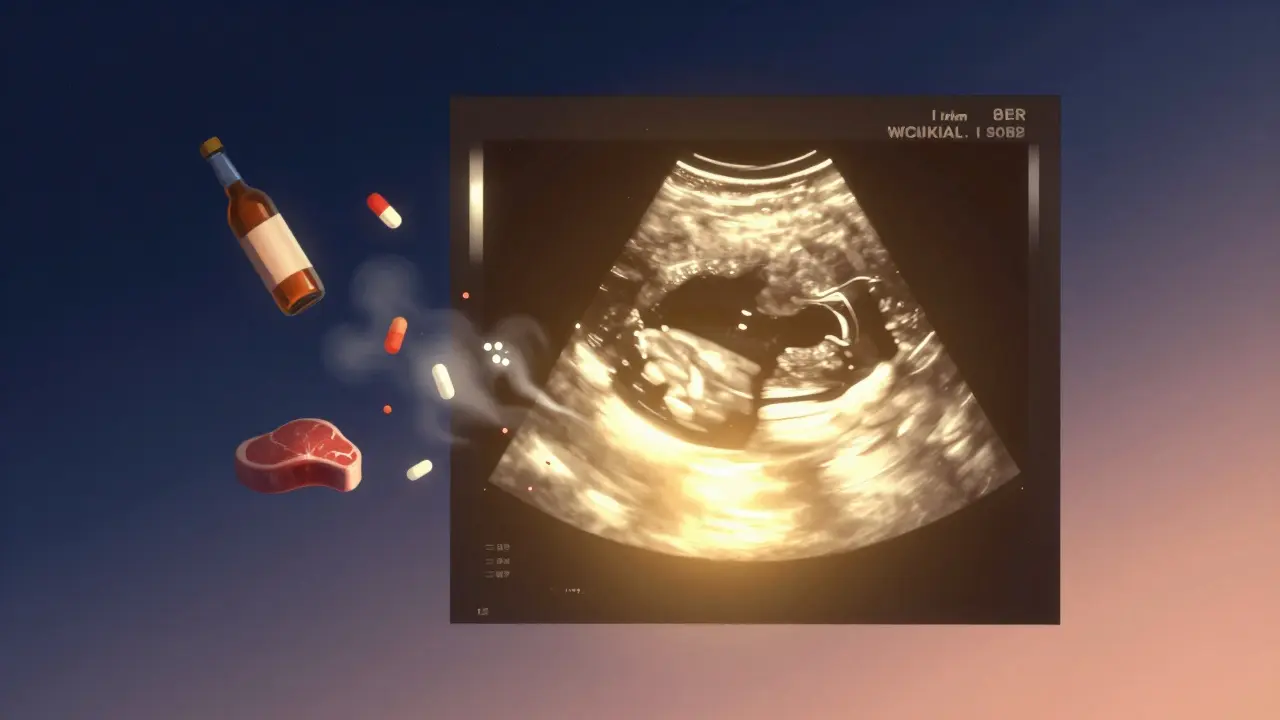

Ultrazvukový obraz srdcového tepu plodu září světlem, které odhání rizikové faktory.